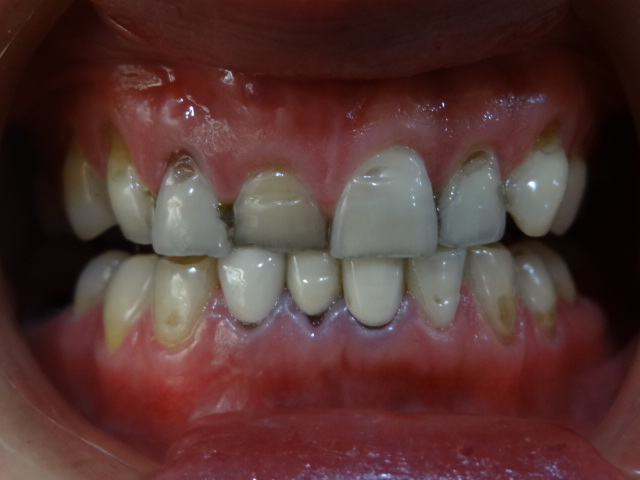

術(shù)前

初中就開始抽煙,我是標準的滿口煙牙,這不過年要去女朋友家里拜訪,為了給她家人留個好一點的印象,衣服買了,鞋子也買了,女朋友說讓我去把牙齒洗一下,不然都不能大笑,沒辦法,細節(jié)也要注意,就去了!